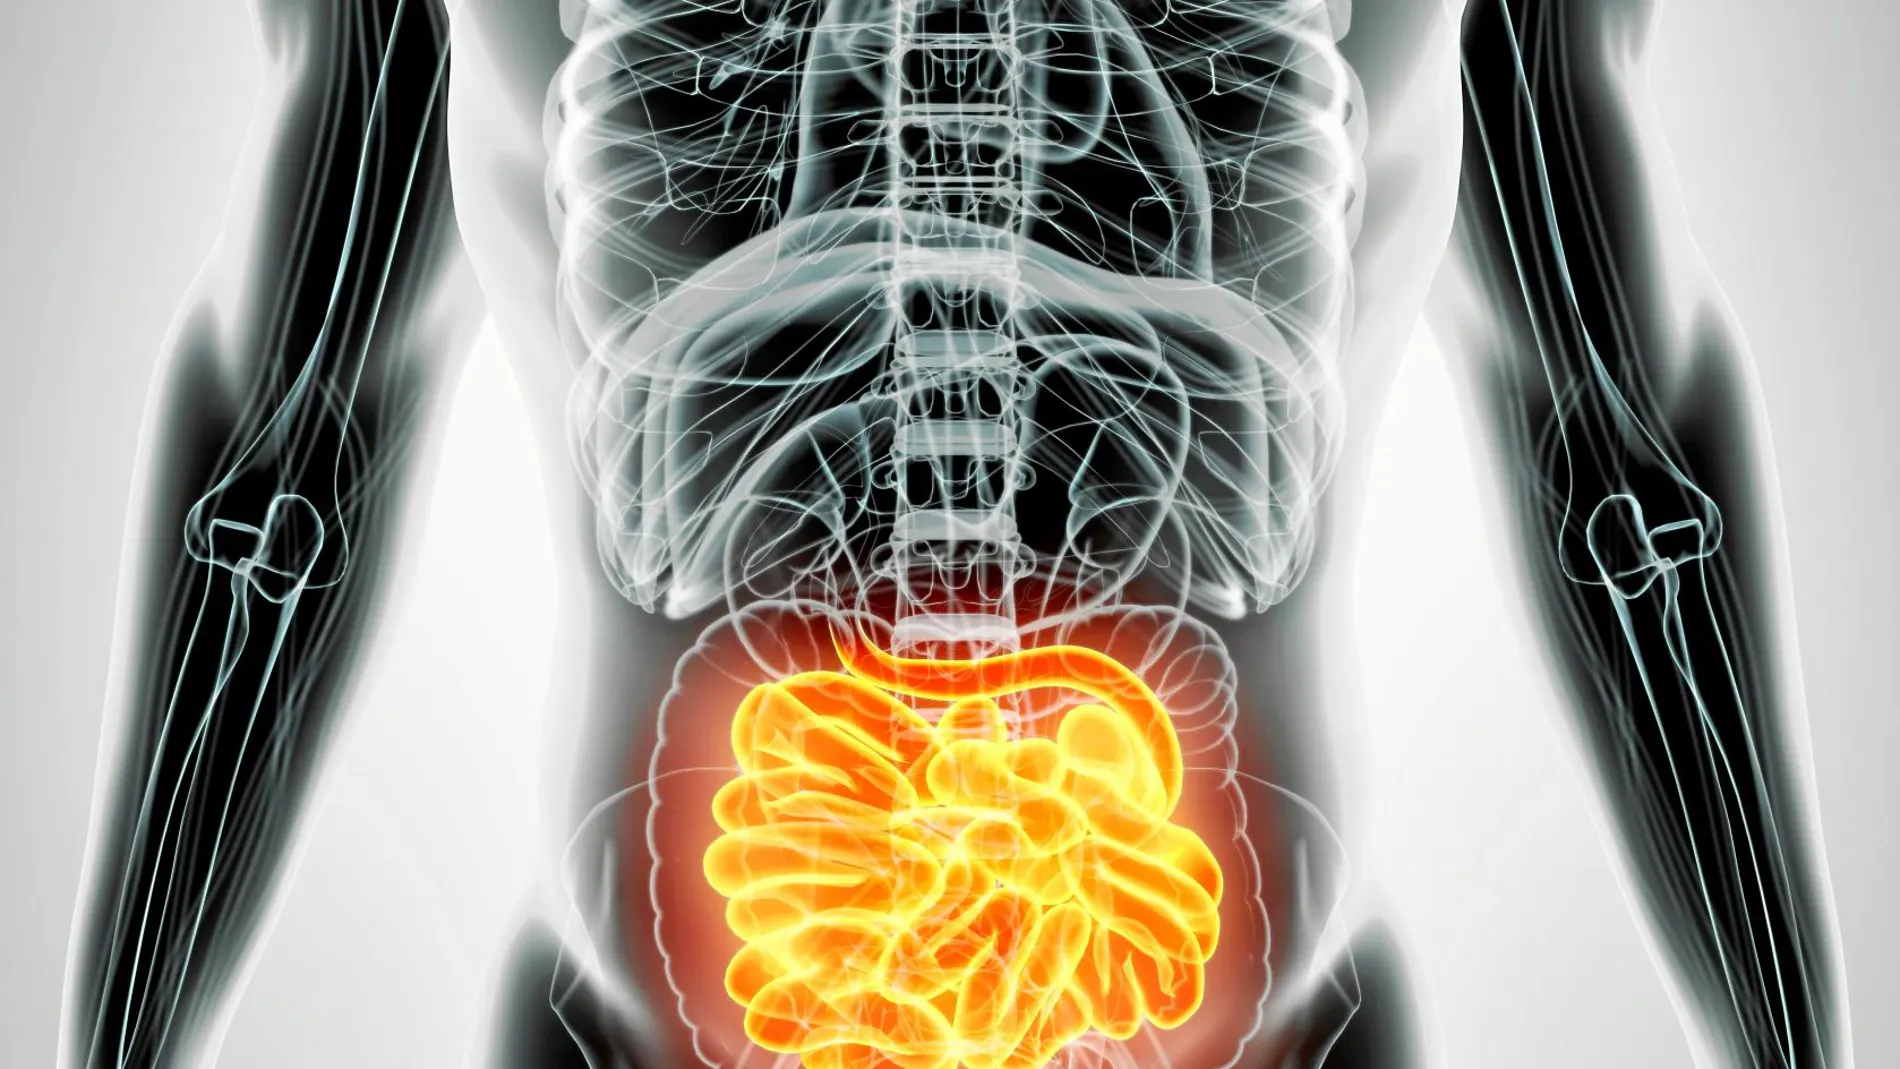

La biota intestinal, rica en bacterias y otros microorganismos, puede ser transmitida de un paciente a otro. Una persona sana puede donar millones de bacterias de su aparato digestivo a una persona enferma con déficits de ese capital bacteriano. El resultado es una capacidad de recuperación en infecciones o en desórdenes inflamatorios.

En la práctica médica y en los laboratorios de investigación, a menudo se encuentra que las heces de un donante son más aptas para provocar mejoras efectivas que otras. Desde hace tiempo, esos donantes especialmente eficaces han llamado la atención de la ciencia. Pero más recientemente, la atención ha crecido de manera considerable. La razón es que nuevos estudios demuestran la influencia de la biota intestinal en el desarrollo de cada vez más patologías. Las bacterias del aparato digestivo se encuentran relacionadas de alguna u otra manera con males como la esclerosis múltiple, el asma, alergias, enfermedades cardiovasculares, cáncer, enfermedades neurodegenerativas y diabetes. Evidentemente, cuanto más se sabe sobre la conexión entre la microbiota intestinal y el resto del cuerpo, más valiosos se vuelven los donantes agraciados por la naturaleza.

Hoy por hoy no se sabe muy bien por qué. Las investigaciones se centran ahora en identificar las peculiaridades físicas y químicas que convierten a estas personas en portadoras de superheces. De momento, existen algunas pistas: presentan una mayor diversidad de especies microbiológicas. De hecho, a la hora de seleccionar donantes, un marcador de eficacia podría ser el análisis del microbioma en busca no solo de grandes cantidades de bacterias y hongos, sino de una gran diversidad. Pero, además, se han encontrado algunas especies de microorganismos que son especialmente deseables. Son bacterias que provocan reacciones químicas de las que carece el enfermo. En el caso del colon irritable, por ejemplo, son muy útiles las bacterias que provocan la síntesis natural del ácido butírico, una sustancia que interviene en la formación de la mucosa gástrica y que protege contra el desarrollo de ciertas patologías.